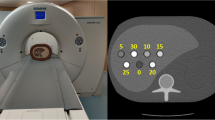

The experimental PCD is a silicon-strip detector with an edge-on multi-strata design (Fig. 1) [19,20,21]. The multiple strata enable the detector to operate at clinical CT count rates since the total count rate is divided among the dedicated electronics in each stratum [23]. Compared to cadmium-based detectors, this allows for handling of high count rates without reducing the pixel size to the degree that charge sharing becomes a dominating effect that reduces the spectral performance of the detector. Each pixel of the PCD consists of nine strata, each connected to a channel of a photon-counting application-specific integrated circuit (ASIC), which sorts photon counts into eight energy bins with configurable thresholds [35]. The detector module has 88 × 50 pixels that are 0.5 mm (in slice) × 0.4 mm (out of slice) at the detector.

The detector pixels were calibrated using a multi-material calibration phantom and a procedure suggested in [36]. The calibration phantom consisted of two plastic step wedges and three contrast agent containers. The step wedges were made of polyethylene (PE) and polyvinylchloride (PVC). These materials span the set of linear attenuation coefficients of human tissue with positive coefficients [37]. They are useful for calibration since they allow for transmission measurements mimicking any combination of tissues found in the human body. The step wedges contained steps of 0, 4, 8, 12, 16, and 20 cm of PE and 0, 3, and 6 cm of PVC, respectively. The contrast agent containers were made of PE, with an internal width of 0.85 cm and external width of 1 cm. They were filled with Visipaque (GE Healthcare) iodine contrast agent and water solution with concentrations of 0, 16, and 32 mg I/ml.